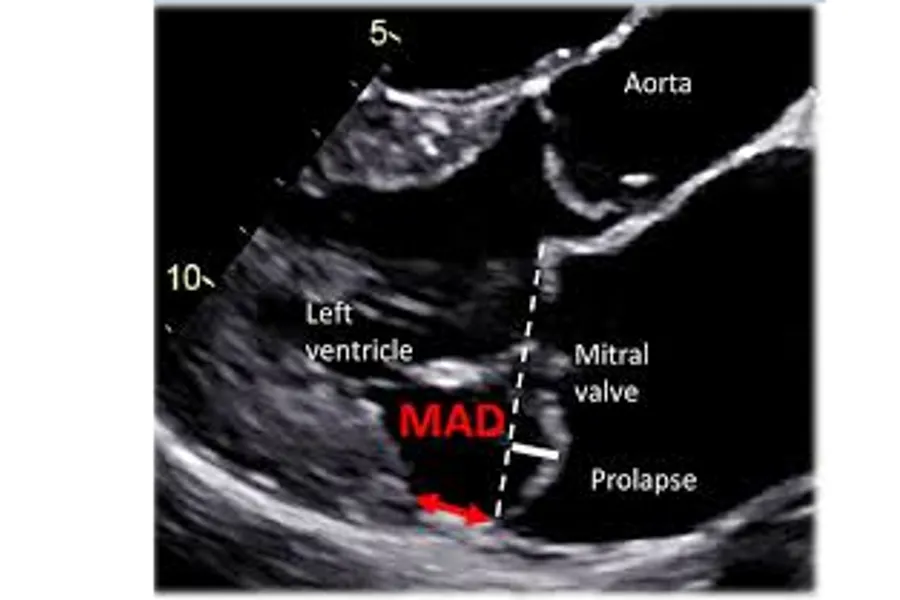

Figur: Lars Dejgaard and Kristina Haugaa, Hjerteforum 2019.

Mitralklaffprolaps (MVP) er en relativt vanlig klaffefeil som påvirker 2-4 % av befolkningen generelt. I de fleste tilfeller er prognosen for individer med denne tilstanden god. Imidlertid er en del av pasientene med MVP i risiko for plutselig hjertedød. De spesifikke mekanismene bak utviklingen av arytmier hos disse individene er for det meste ukjent. Mitral annular disjunction (MAD) er en av de arytmogene risikofaktorene. Den genetiske bakgrunnen for både MVP og MAD er fortsatt stort sett ukjent, og effektive terapeutiske strategier mangler.